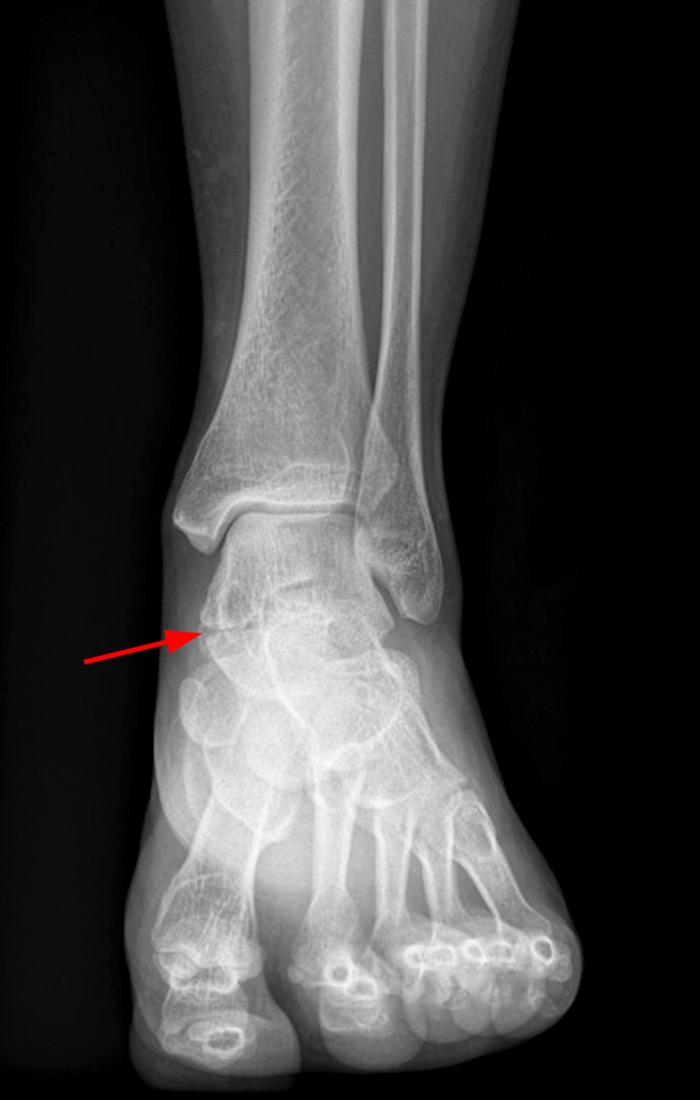

From radiopaedia.org

Image Talus Bone Growth Plate A talus fracture can cause. • traumatic growth arrests have better outcomes than treating a growth plate pathology secondary to infection, metabolic bone disease or ischemia Specific applications including fractures of the lateral process,. Most growth plate fractures occur in bones of the fingers, forearm and lower leg. The growth plate in the ankle, also known as the epiphyseal plate,. Talus Bone Growth Plate.